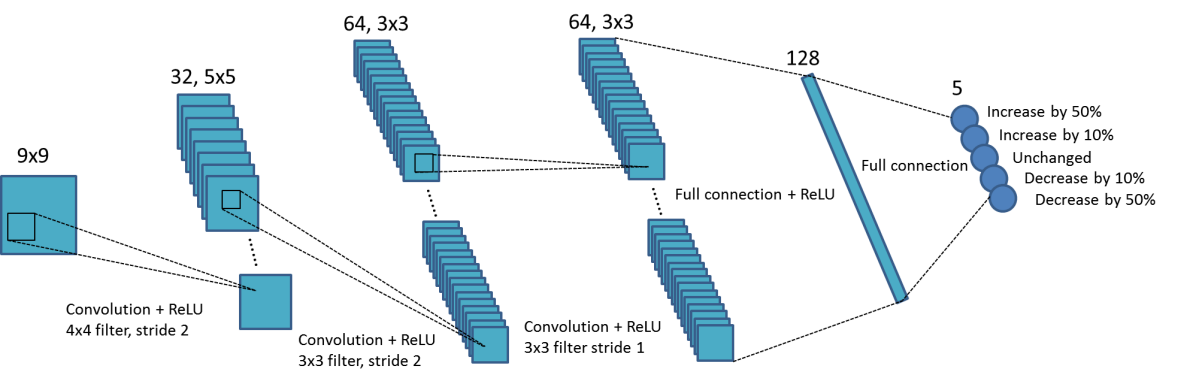

Under this framework, we parameterize the value function using a convolutional neural network, where are network parameters. This network is referred as Parameter-Tuning Policy Network (PTPN) from here on. The structure of the network is depicted in Fig. 2. will be determined through a reinforcement learning process, as will be described in the next section.

where is the reward at iteration step , is a discount factor, and stands for the parameter tuning policy: taking an action after observing a state . Here, we consider a deterministic policy that generates a unique action based on the observed state . Specifically, we follow a greedy strategy that selects the action maximizing the value under the input , i.e. . In the particular problem of interest here, the state is an image patch . We consider five possible output actions: keeping the parameter unchanged, increasing or decreasing it by , and increasing or decreasing it by . We choose the values of or as possible amounts of changes in the system, as we expect these values will not critically affect the capability of parameter tuning of our system.